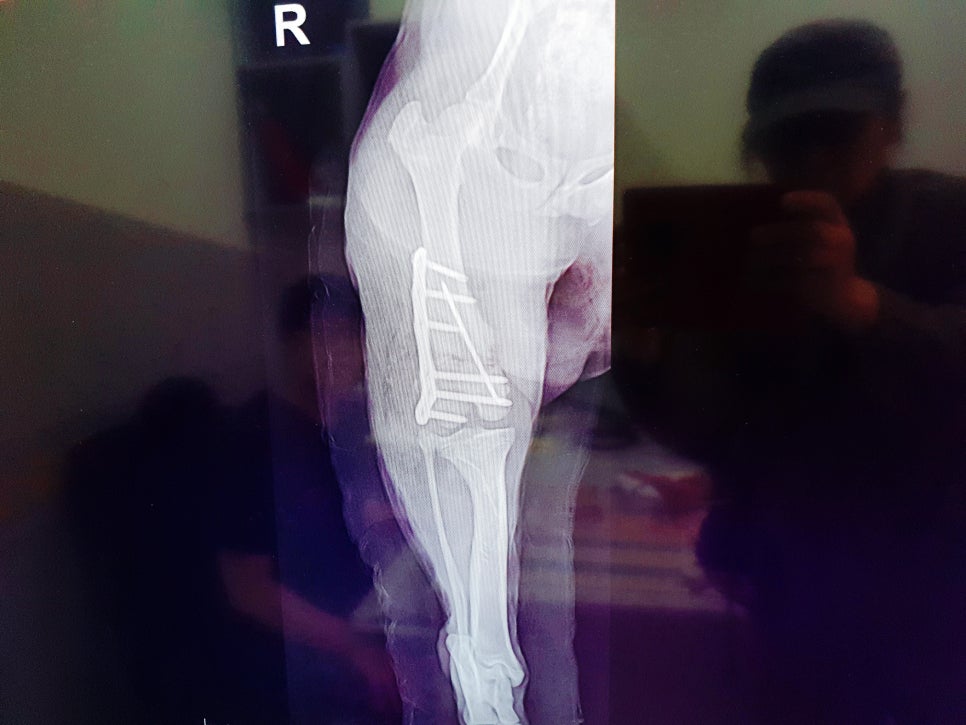

다리 엑스레이를 찍어 보니

아니나 다를까 뒷다리 오른쪽이

골절이 된상태로 적어도

골절후 2주 이상은

지난것 같다고 하더라고요

바로 골절이 된것을 치료하는 것과

시간이 지난 상태로 수술을 하는 것은

많은 차이가 있는데 이미 부러진 다리

뼈들이 제멋대로 붙어지고 있어서 그 뼈들을 다시

제자리를 잡고 맞추면서 수술을 한다고

하더라고요. 그래서 더욱 아프고 힘든 수술

설탕이는 뒷다리에 임플란트로

고정을 해서 평생 임플란트를

심고 살아야 한다고 하더라고요